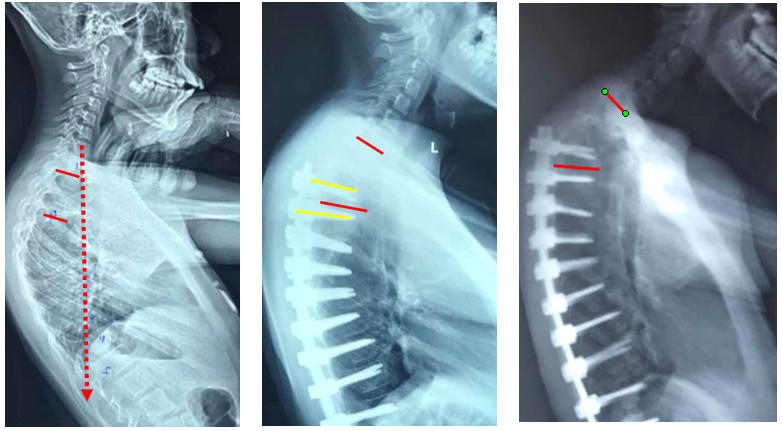

图23 选择合适的UIV

1.选择合适的UIV

(1)固定近端交界性后凸角>5°的区域应包括在融合区内;

(2)胸椎后凸过大患者,融合水平应跨过胸椎后凸节段到上胸段;

(3)尽量跨过交界区,如胸腰段尽量不终止于T11和T12;

(4)颈7铅垂线距离UIV不要太远;

(5)矢状面上UIV上方椎间隙无后凸角度。